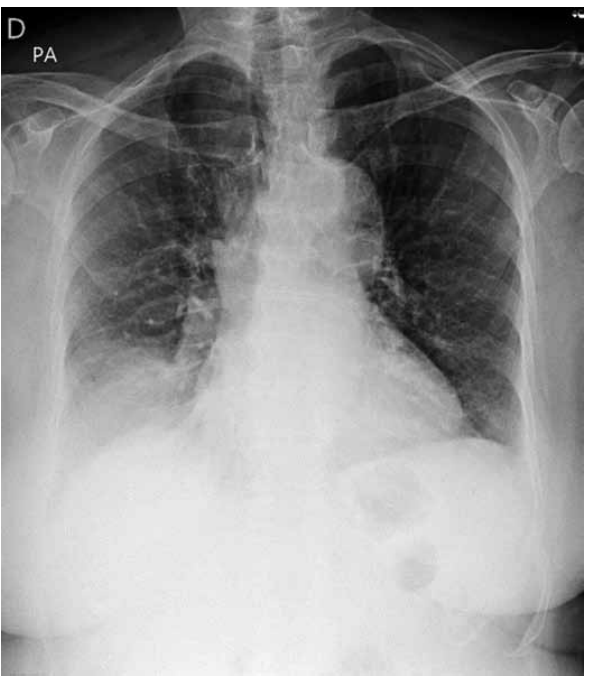

A radiografia apresenta a seguinte alteração compatível com o envelhecimento: